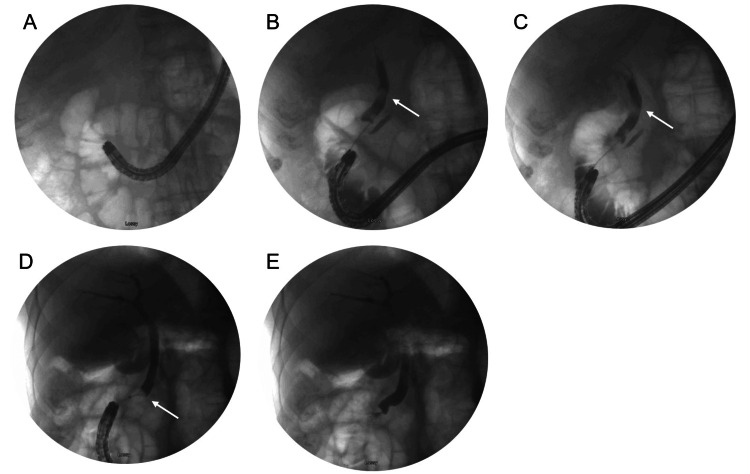

The patient was placed supine and general anesthesia was employed. A duodenoscope (EVIS EXERA II, TJF-Q190V, Olympus, Center Valley, USA) was inserted without difficulty into the stomach, at which point it became apparent the patient had had an antrectomy with Billroth II anastomosis. The efferent and afferent limbs were not easily differentiated. Each limb was explored with the duodenoscope, but due to angulation, the scope could not accurately identify the ampulla of Vater. A gastroscope (EVIS EXERA III GIF-HQ190, Olympus, Center Valley, USA) was then used to identify the afferent limb. There was initial difficulty with advancing the scope into the afferent limb, but eventually, the duodenal stump was reached and the ampulla was identified (Figure 2A). The ampulla was cannulated with a wire and a Hydratome RX 44 sphincterotome (.035"/260cm, Boston Scientific, Marlborough, USA) was advanced into the duct. A cholangiogram showed a 1.0 x 0.5 cm distal stone but otherwise normal ductal anatomy (Figure 2B–2C). A sphincterotomy was performed at approximately the 6 o’clock position accounting for the patient’s supine positioning (Figure 3A). Next, we attempted to advance an Extractor Pro RX Triple-lumen Retrieval Balloon (Boston Scientific, Marlborough, USA) over the guidewire; however, it was too thick for the channel of the gastroscope. The wire from a Jagtome Revolution RX 39 sphincterotome (.025”/260cm, Boston Scientific, Marlborough, USA) was used to cannulate the duct. As this wire had a smaller diameter, the retrieval balloon was able to be threaded over this wire and through the gastroscope channel. Some debris was removed, but the filling defect persisted. The balloon and wire were removed, and a FlowerBasket stone retrieval basket (8 WIRE, 190cm X 20mm, Olympus, Center Valley, USA) was advanced into the duct (Figure 2D). We were able to fragment the stone and witness its removal (Figure 3B). We removed the remaining debris with the balloon and performed a balloon occlusion cholangiogram which showed no filling defect (Figure 2E).